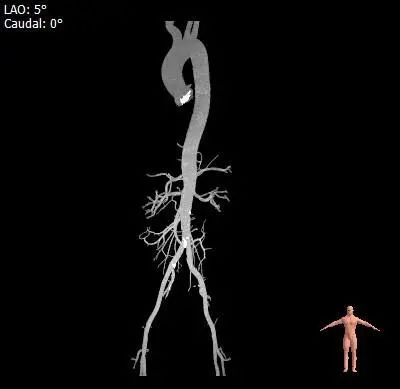

双侧髂动脉未见明显扭曲,股动脉穿刺区域未见钙化斑块,入路血管直径良好。

外周血管及主动脉弓解剖